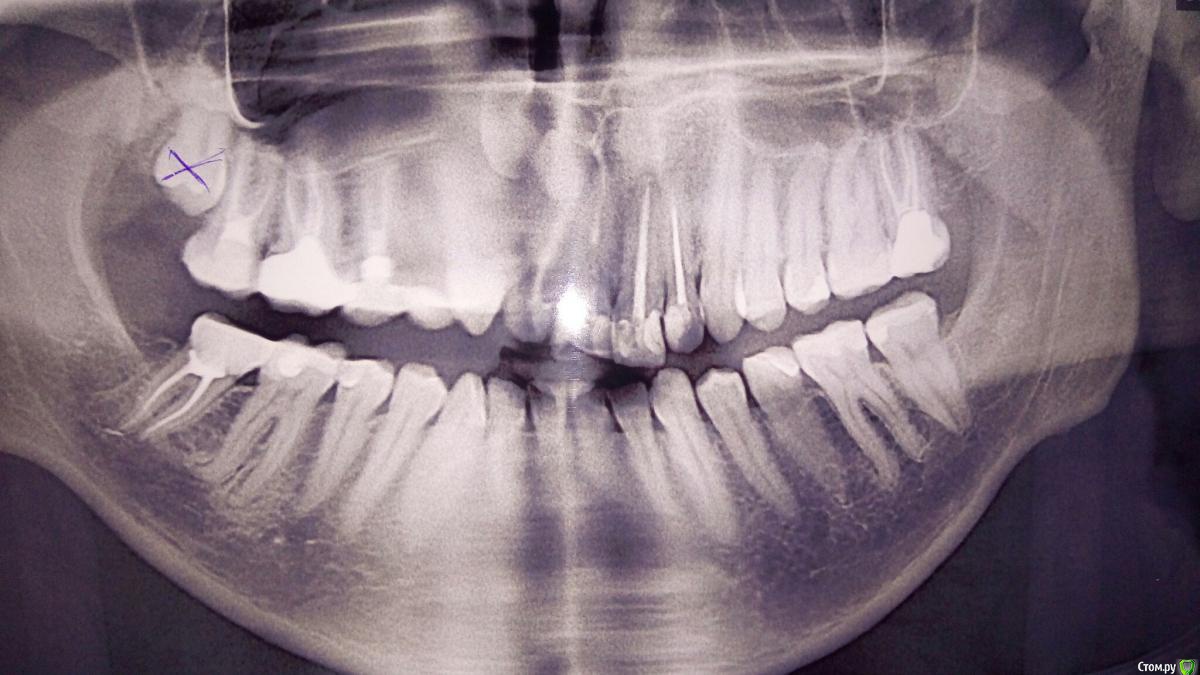

ijaija Опубликовано 30 апреля, 2017 Поделиться Опубликовано 30 апреля, 2017 Нужна помощь стоматолога, подскажите по рентген. снимку!Месяц назад в плановом режиме обратился к терапевту, чтобы привести в порядок зубы.Она пролечила несколько зубов кариеса и я пошёл домой. Через 5 дней начались сильные боли справа сверху, причём сложно понять где именно.Я пришёл к врачу и попросил сделать снимок, она без снимка простучав, выяснила что именно в 5 зубе проблема, который она лечила, якобы там пульпит. Решительно стала его сверлить, поставила лекарство, потом через 3 дня почистила каналы и поставила пломбу.После пломбировки пошёл на панораму (фото-приложение 1) Стало видно зуб мудрости который сдвигает соседние зубы и давит на них.Боли продолжились, стали ещё интенсивнее и стали отдавать в висок, скулу и затылок. Было решено удалять мудрости.Через 3 дня удалил мудрости, причём ретинированный, всё прошло успешно, через 3 дня опухлость прошла, боль от удаления прошла, но вернулась та боль, что была в начале и сильно отдаёт в висок и чихаю. Утром не беспокоит, болит после 15-16 и до 1 ночи. причём особенно после еды, когда хорошенько прополощу - отступает. Температура иногда повышалась до 37.0 не более.Пью обезболивающие но они плохо помогают. Ходил сегодня к дежурному врачу в поликлинику, сказал что после удаления всё заживает нормально. Помогите пожалуйста, может по моим рассказам или по снимкам хоть что-то станет понятно..Заранее благодарю! Ссылка на комментарий

shishok Опубликовано 30 апреля, 2017 Поделиться Опубликовано 30 апреля, 2017 Я бы 46 проверила. 1 Ссылка на комментарий

Fake personage Опубликовано 1 мая, 2017 Поделиться Опубликовано 1 мая, 2017 Стоит обратить внимание на предпоследний зуб справа внизу Ссылка на комментарий

Pan Опубликовано 2 мая, 2017 Поделиться Опубликовано 2 мая, 2017 а четвёртый лечили тоже недавно? Нужны ещё дополнительные снимки. По этим не определить проблемы. И да, нижний шестой правый нужно протестировать. Ссылка на комментарий

St. Опубликовано 5 мая, 2017 Поделиться Опубликовано 5 мая, 2017 странно что не 6, как многие здесь говорили.. На обоих - 5 и 6 объемные пломбы, так что определить можно только в кресле у стоматолога.Хорошо что разобрались! Ссылка на комментарий

ijaija Опубликовано 12 мая, 2017 Автор Поделиться Опубликовано 12 мая, 2017 Дело было в шестом зубе снизу! Не выдержал, поехал к платному стоматологу и сказал чтобы проверил 6! на снимке было видно что пломба проходит будто сквозь пульпу, когда врач рассверлил, сказал что пульпа наполовину погибла и воспалена, наложил лекарство. Сейчас пятый залечили наложили пломбу, но она не выпуклая как с противоположной стороны, а немного углубленная по форме, это ничего страшного? Или у каждого врача своя пломба?) Ссылка на комментарий